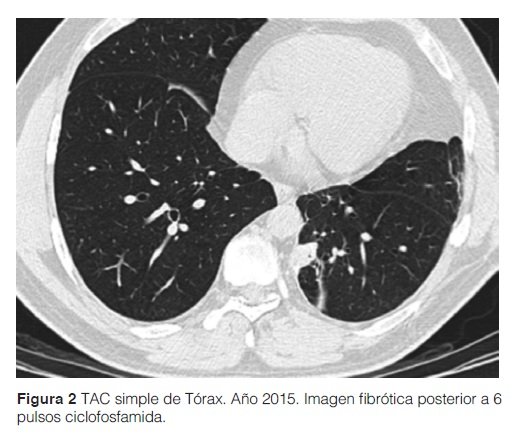

Ante este diagnóstico de ER-IgG4 el paciente recibe tratamiento con prednisona a dosis de 15 mg/día y azatioprina dosis ascendentes hasta 150 mg/día, sin respuesta favorable a los 12 meses. Se practica TAC contrastada de tórax 12 meses después de inicio de tratamiento, donde se encuentra una imagen nodular de similares características. Se procedió a rebiopsia de dicha imagen nodular donde se informa infiltrado intersticial linfoplasmocítico con invasión marcada de pared de vasos sanguíneos de mediano calibre; una segunda inmunohistoquímica informó resultados similares al anterior. Se inicia ciclofosfamida (CFM) ante diagnóstico de una probable vasculitis linfoplasmocítica y enfermedad pseudonodular por IgG4, con mejoría clínica. En la TAC torácica con contraste de control a los 6 meses del inicio de CFM se informa ausencia de nódulos pulmonares; en su lugar se observan finos trazos fibróticos con retracción de la pleura. (ver Figura 3)